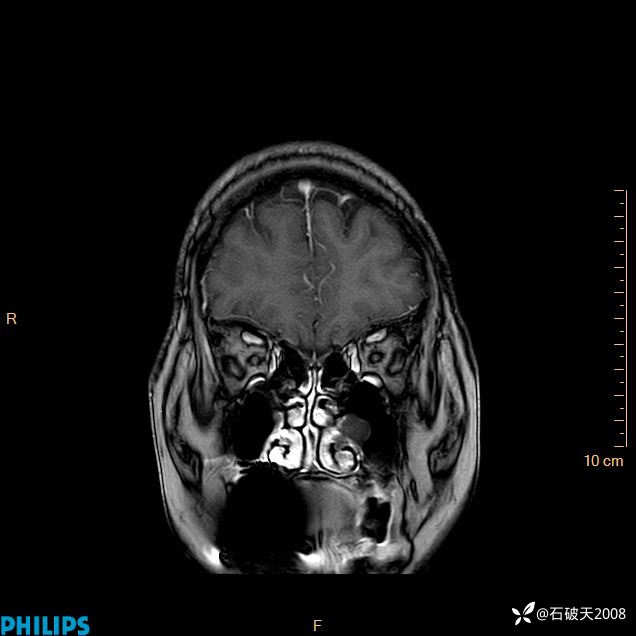

2024.2.21MR

增强冠状位